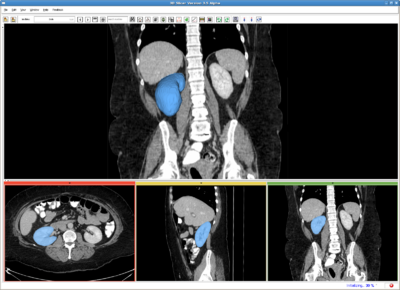

Multi-Object RSS (MORSS)

RSS result for abdominal CT image

In contrast to the above single object RSS, in MORSS, the user can use different label (color) to draw the seed label image. After that, the algorithm detect the number of objects and evolve multiple contours simultaneously.

The basic steps of MORSS is the same as RSS. In fact, if only one type of seed is given (one non-zero label), the MORSS is in fact the single object RSS above.

Moreover, since the number of labels are determined after the algorithm starts, on the user interface, it is difficult to adjust the parameters for each of the target object. Therefore in the current version, the same parameters set on the GUI apply to all the contours. This, however, may not be desirable in all cases. Similar situation is for the expected volume. So on the GUI, we didn't ask for the expected volume. Instead, we used a more engineering term "number of iterations", which also applies to all the contours.